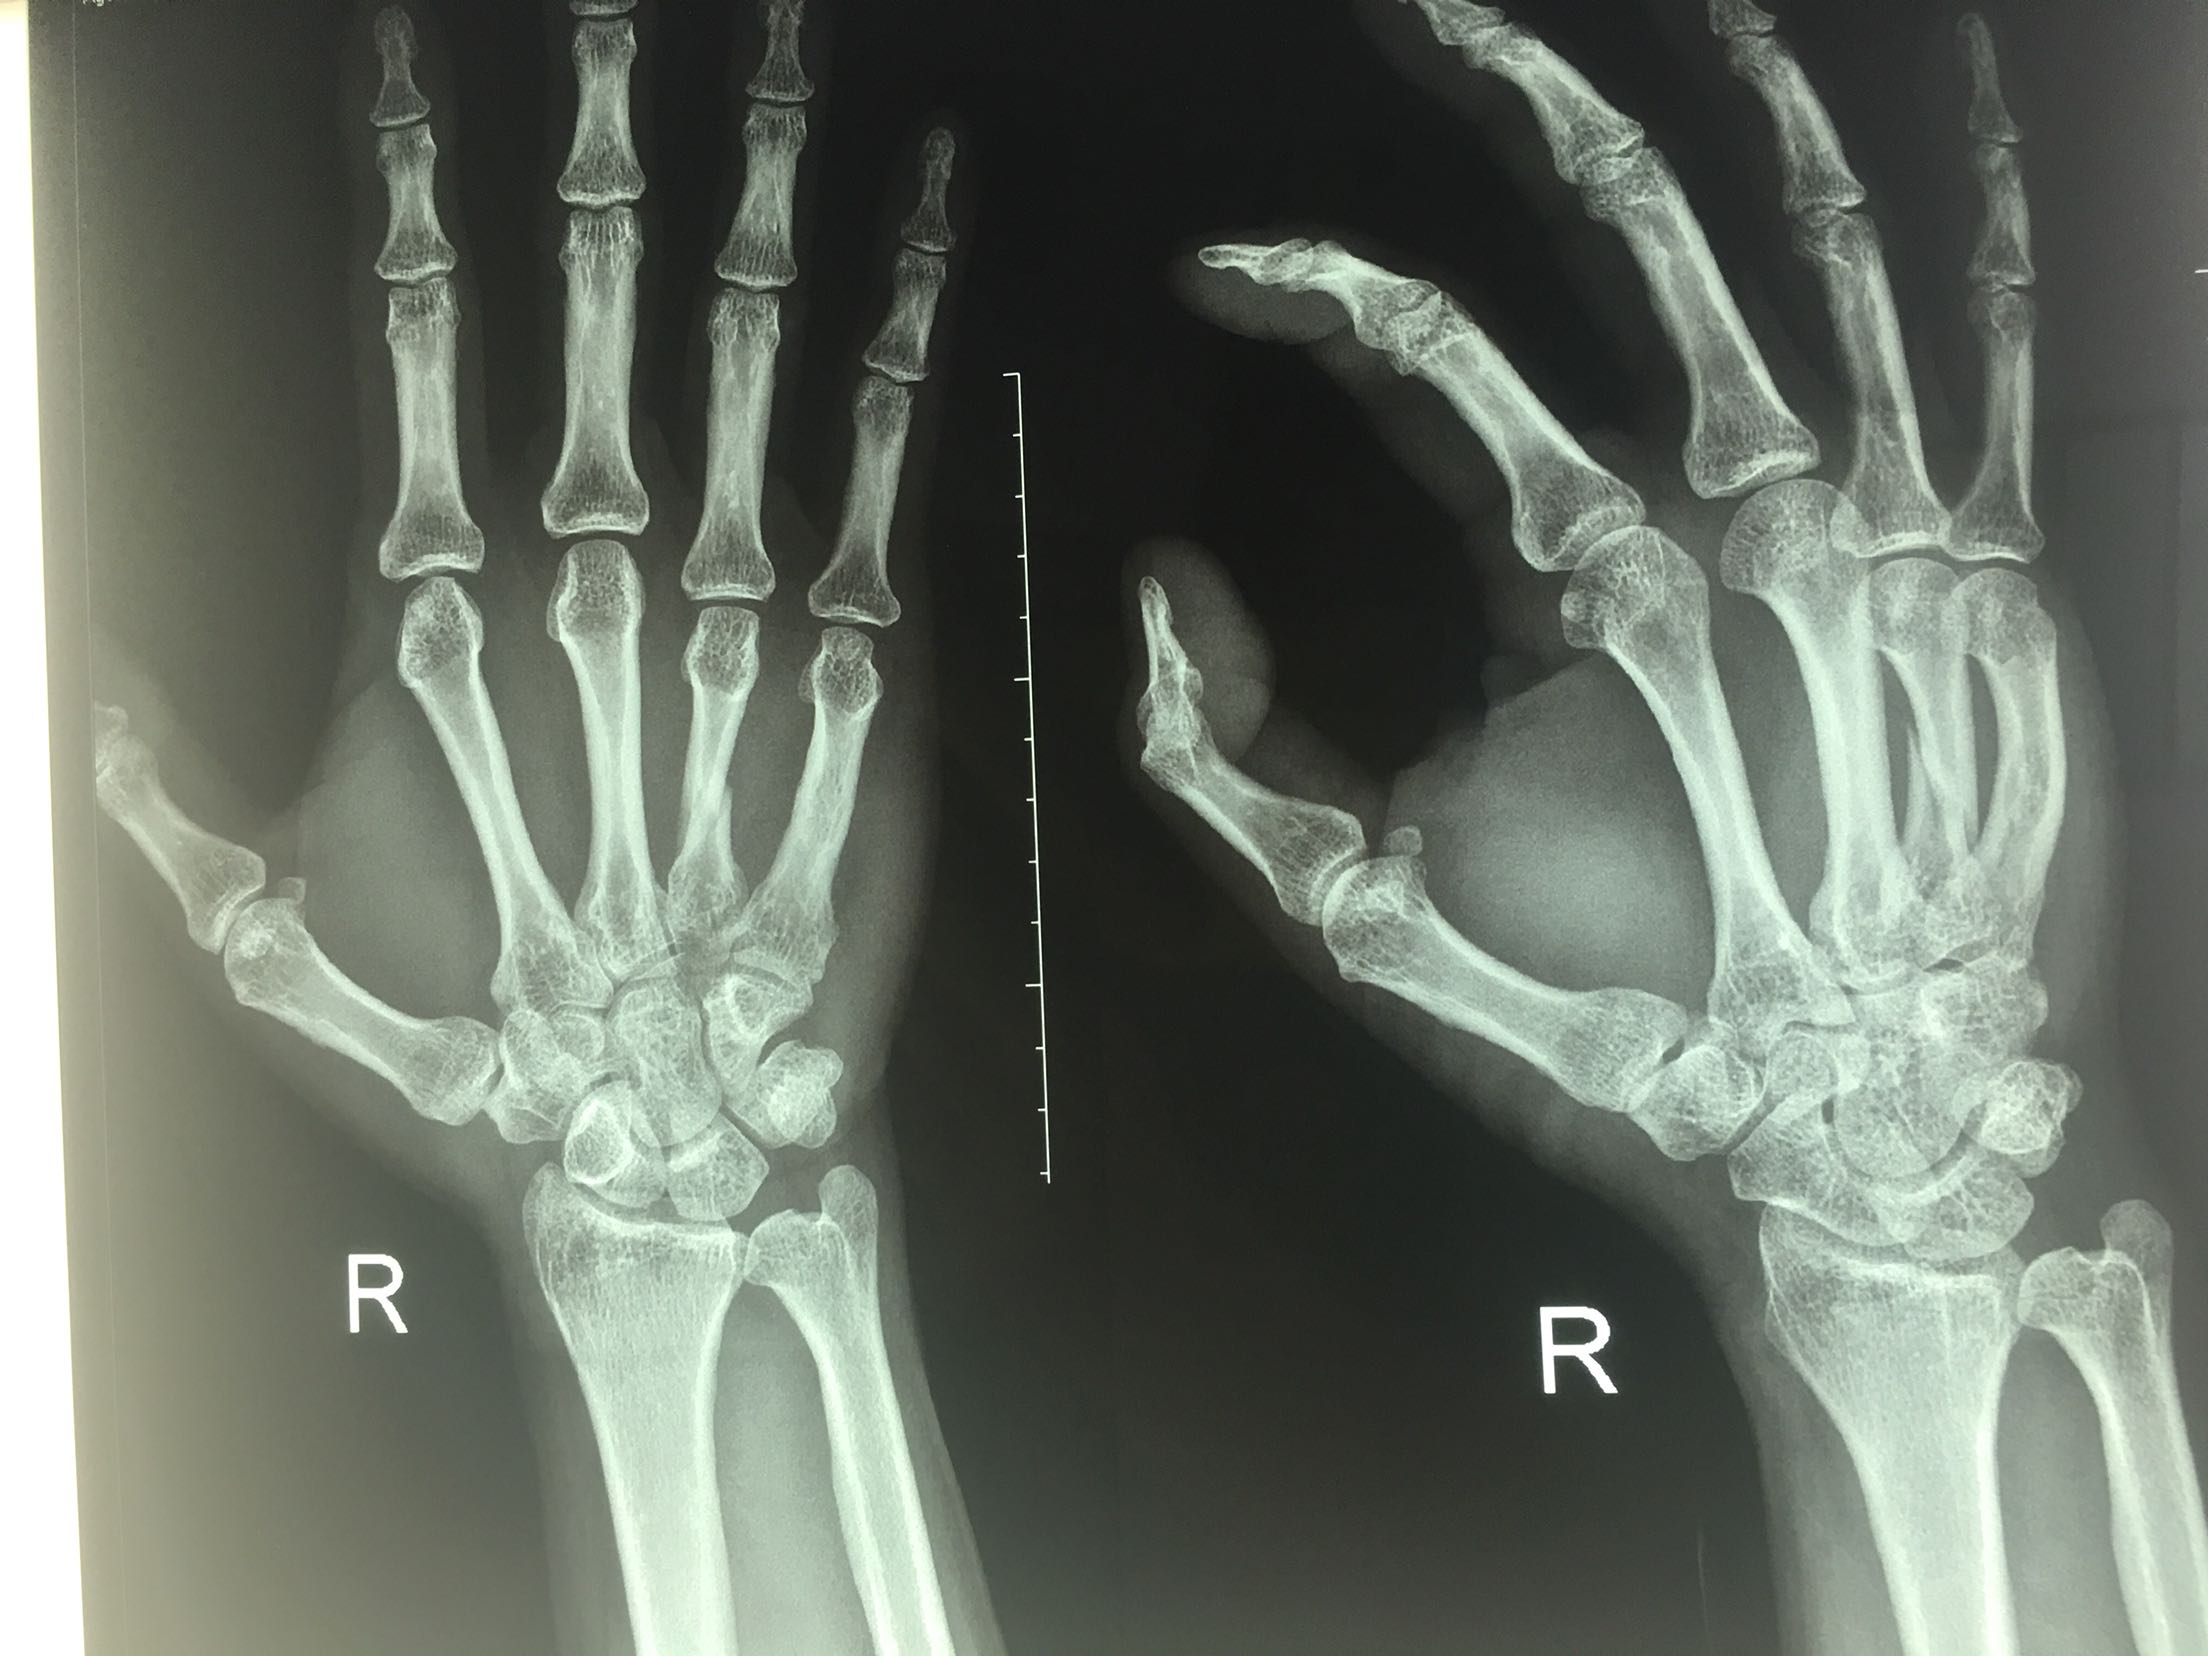

拇指锤状指,掌骨骨折(切复内固定)

骨折 锤状指 掌骨骨折

患者,男,51岁,电钻挤打伤后右手,肿痛,活动受限1小时入院。既往身体健康,无特殊不良嗜好。

右手大拇指呈锤状改变,掌背侧肿胀明显,皮色发红,皮温高,局部压痛,第四掌骨纵叩痛阳性,局部活动障碍,末梢血运感觉正常。

积极术前准备,在臂丛麻醉下行锤状指伸指功能重建术,掌骨骨折切复内固定术,术后抗炎,消肿对症处理。<img src=https://pub-voice-video.medlinker.com/9129333F-3928-47F0-B39A-978756FECFAD><img src=https://pub-voice-video.medlinker.com/945D4FD6-D0B7-41EF-ABB0-C2940D6C2E54><img src=https://pub-voice-video.medlinker.com/2F847276-23A8-4CAF-BF99-1828976F7BAD><img src=https://pub-voice-video.medlinker.com/2996EABA-9281-4CC0-8612-66A515AC6472><img src=https://pub-voice-video.medlinker.com/D3EFB6D4-D26D-4778-B65E-2D52DD5235E7><img src=https://pub-voice-video.medlinker.com/9197F543-FC48-48BB-BA43-DDBEEE8749C0><img src=https://pub-voice-video.medlinker.com/109E9BC2-A473-4E71-B880-027E2D1DF300>

每一例锤状指都不一样?大拇指伸肌腱相对厚实一些!!!临床经验丰富的提升有很大帮助!!!